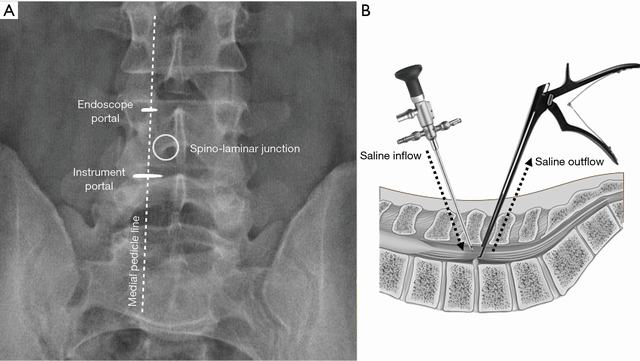

为了获得真实的正位X线影像,应平行于椎间盘透视,透视后标记皮肤。UBE减压需要在深筋膜上做两个小切口:一个较小的切口约5–6 mm,用于插入观察内镜和连续的生理盐水冲洗;用于器械操作和生理盐水流出的内镜切口较大约8–10 mm(图2)。具有0度或30度范围的内镜系统是必不可少的。

图2(A)圆圈表示最初的目标区域,即棘突-椎板交界处。观察通道和操作通道的皮肤切口沿椎弓根内侧线分布,相距2-3 cm;(B)示意了观察通道和操作通道的角度、生理盐水进出情况。

减压的最初目标区域是在棘突-椎板交界处(棘突与椎板下缘的交界处)。两个通道皮肤切口通常沿着椎弓根内侧线放置,相隔2–3cm(图2)。使用长10毫米的软组织扩张器分离椎旁肌,随着生理盐水的流入会产生一个很小的空间并可供使用。进行细致的止血可以使整个手术过程可以在清晰放大的手术视野中进行(图3)。对于小的硬膜外静脉出血和骨面渗出,可以通过调节生理盐水流入流出的静水压来实现止血,软组织内和硬膜外较大的静脉出血可以用等离子刀头止血,松质骨引起的明显出血可以用骨蜡进行止血。